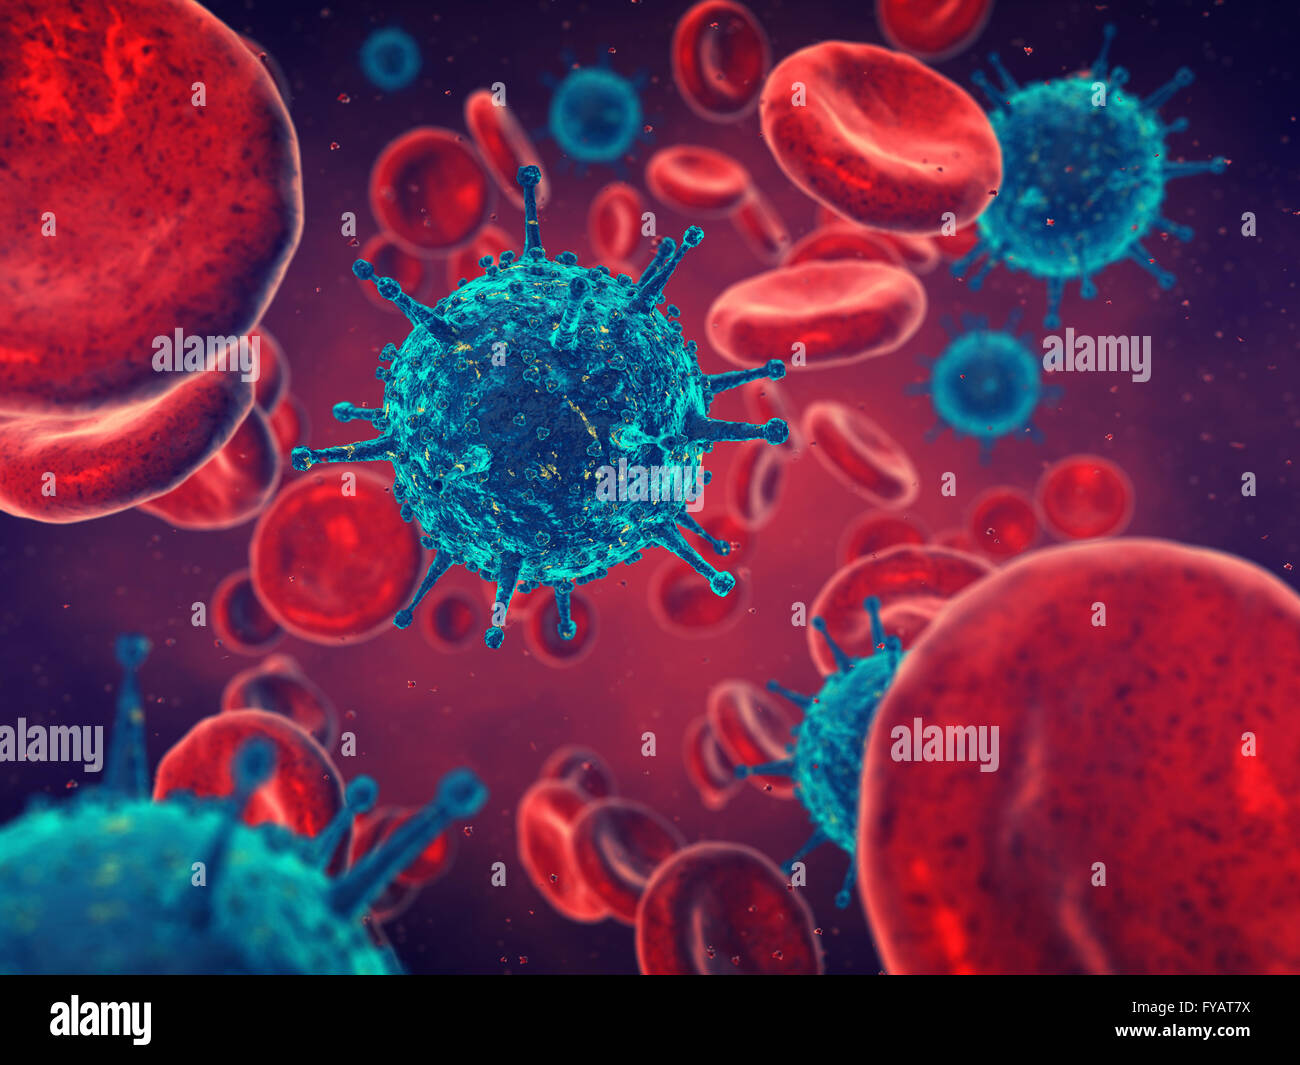

Viruses and red blood cells , contaminated blood , Disease Stock Photohttps://www.alamy.com/image-license-details/?v=1https://www.alamy.com/stock-photo-viruses-and-red-blood-cells-contaminated-blood-disease-102886110.html

Viruses and red blood cells , contaminated blood , Disease Stock Photohttps://www.alamy.com/image-license-details/?v=1https://www.alamy.com/stock-photo-viruses-and-red-blood-cells-contaminated-blood-disease-102886110.htmlRFFYAT7X–Viruses and red blood cells , contaminated blood , Disease

Viruses and red blood cells , contaminated blood , Disease Stock Photohttps://www.alamy.com/image-license-details/?v=1https://www.alamy.com/stock-photo-viruses-and-red-blood-cells-contaminated-blood-disease-125181503.html

Viruses and red blood cells , contaminated blood , Disease Stock Photohttps://www.alamy.com/image-license-details/?v=1https://www.alamy.com/stock-photo-viruses-and-red-blood-cells-contaminated-blood-disease-125181503.htmlRFH7JE7Y–Viruses and red blood cells , contaminated blood , Disease